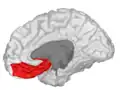

Orbital gyrus shown in red.

Lateral orbitofrontal cortex

Medial orbitofrontal cortex, inner slice view.